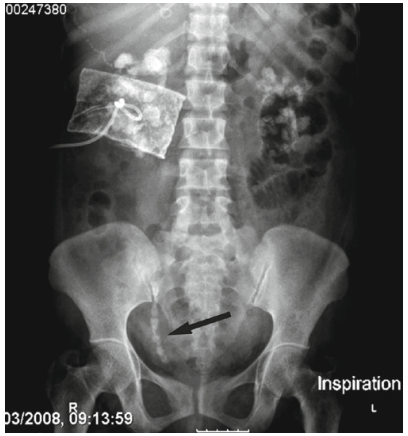

Sự bất thường về giải phẫu như cột sống chia đôi (hình 4) hay vẹo – gù cột sống cũng có thể là yếu tố ảnh hưởng đến TSNCT vì không thể đặt tư thế bệnh nhân chính xác và cố định trên bàn tán sỏi.

7

Hình 7.Sỏi thận trái trên bệnh nhân bị dị tật cột sống chia đôi